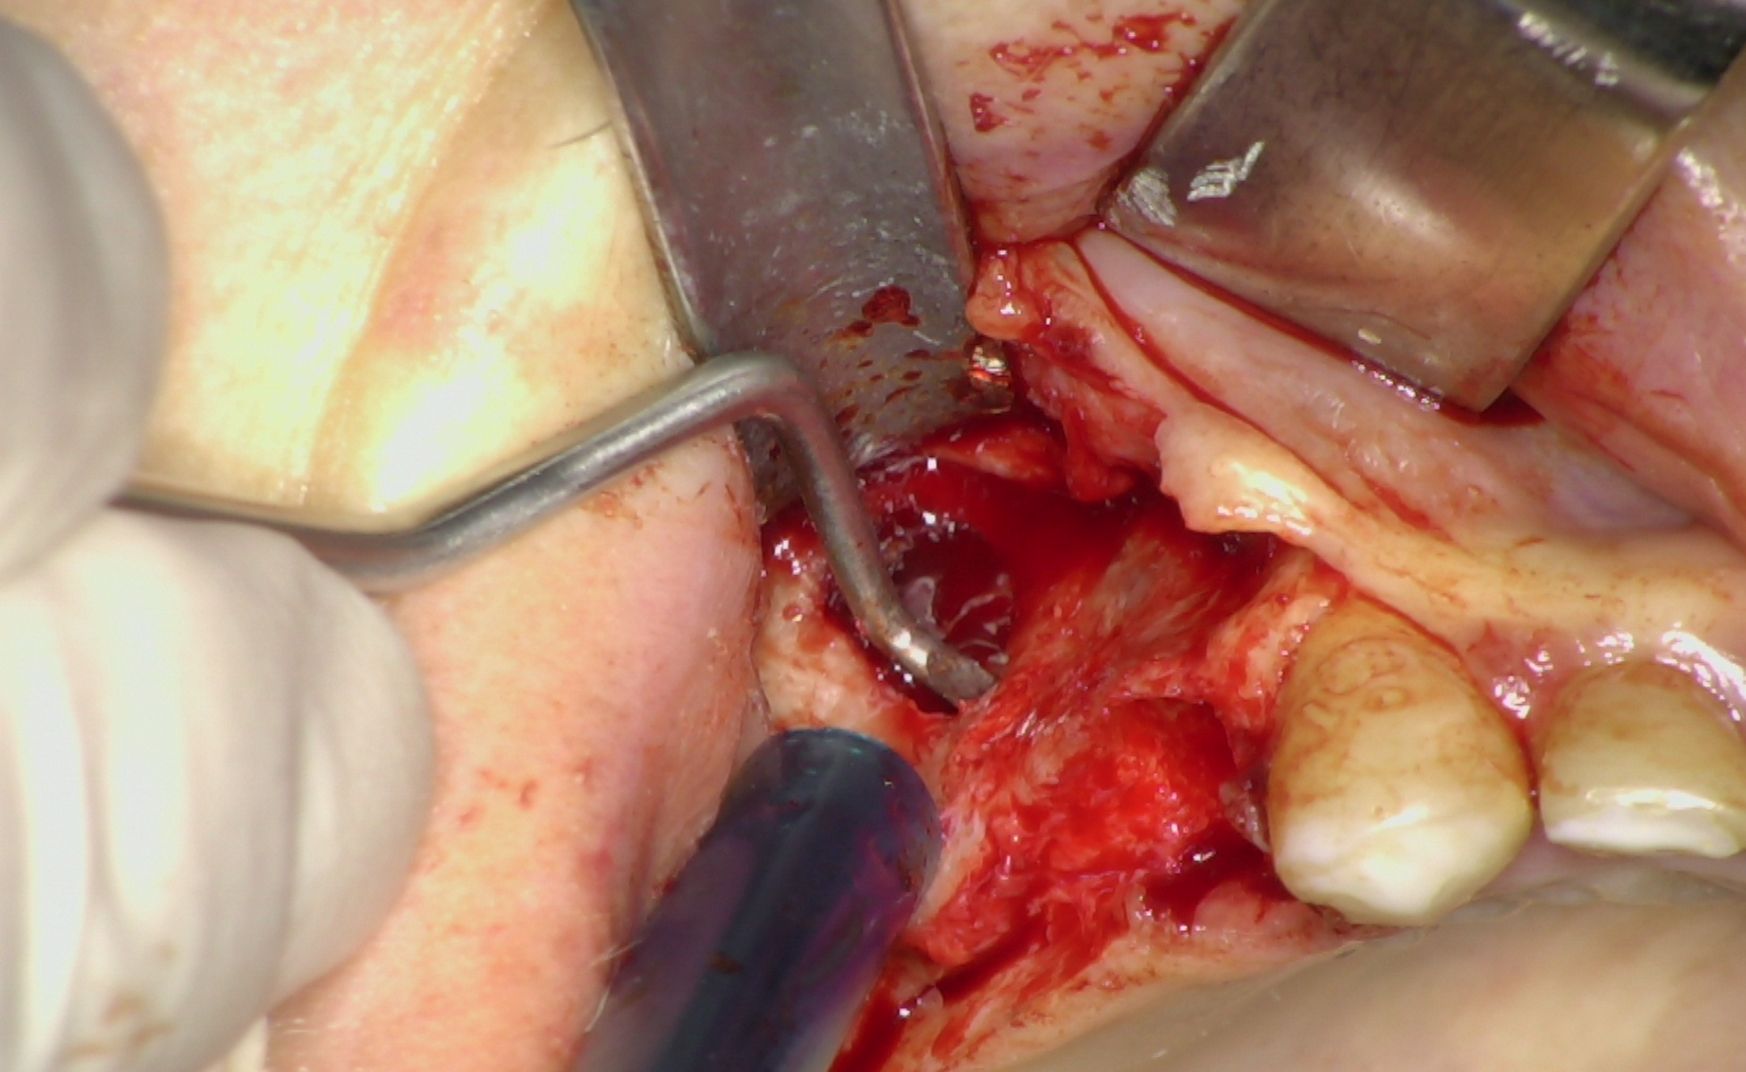

Nei settori posteriori, caratterizzati da significativa atrofia ossea e da pneumatizzazione del seno mascellare, è stato adottato un approccio transinusale. È stata pertanto realizzata una finestra laterale per consentire il sollevamento della membrana di Schneider (Fig. 3), procedura eseguita con particolare attenzione per preservarne l’integrità. Successivamente i siti implantari sono stati preparati con una traiettoria inclinata che attraversa la cavità sinusale, permettendo l'ancoraggio nell'osso basale anteriore. Sono stati quindi inseriti due impianti BT-Rhyno (Fig. 4), progettati specificatamente per l'inserimento transinusale e in grado di garantire adeguata stabilità anche in presenza di ridotto spessore osseo crestale.

Fig. 3 - Membrana di Schneider